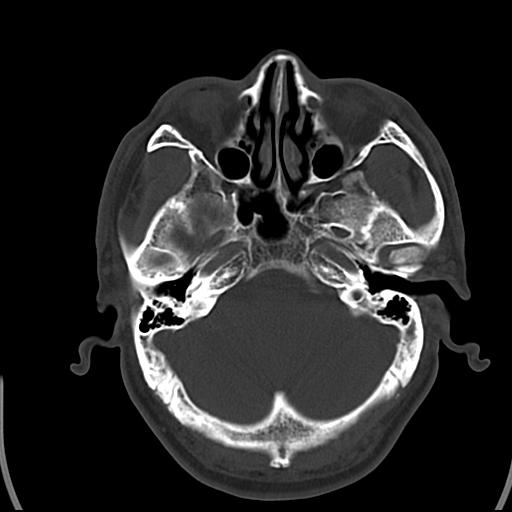

头皮下高密度结节影???临床上在老年男性比较常见。大家看看是什么?成因是? 本例患者,男性,51岁。外伤来诊。无染发史及发根植入史。

皮下钙化点

没见过,可能为毛囊钙化。

考虑钙化。